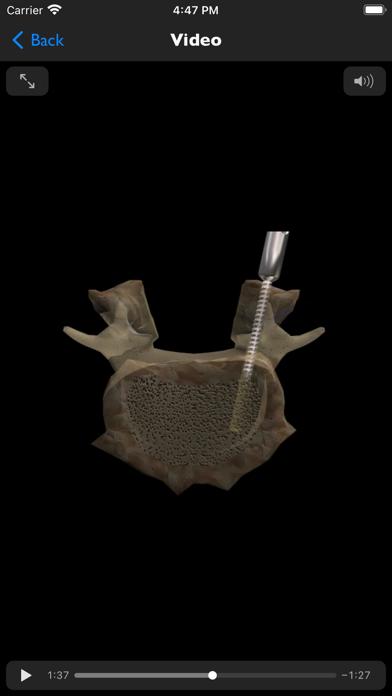

iSpineOperations is an information resource for common spine surgery procedures. It is a presentation library of surgical visualizations, medical images and educational notes. Whilst this app is primarily for clinicians providing patient education, it can also be useful to anyone who wants to know more about spine surgery goals and techniques.

iSpineOperations provides accurate spine surgery goal & technique visualizations for informed consent and education. Medical imaging shows real world examples and educational notes cover the indications, alternatives, expectations and complications.

- ALIF with bone+plate or cage, corpectomy with bone+plate, cage, cage+plate, pedicle screw fusion, PLIF with bone or cage, TLIF with bone or cage